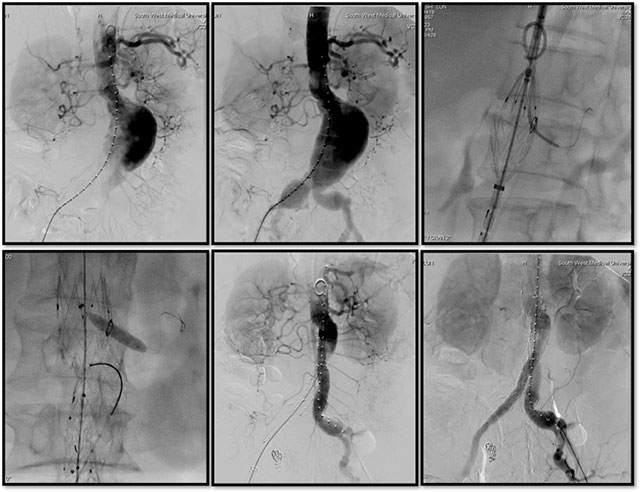

术中支架开窗

由于患者动脉瘤的瘤颈较短(距离左肾动脉不足10mm),经过全科讨论后决定为患者实施腹主动脉瘤覆膜支架腔内隔绝术(EVAR),术中在体外预开窗覆膜支架重建左肾动脉以延长支架近端锚定区。

术中影像

一切术前准备就绪后,斯光晏主任带领团队在全麻下为王大爷实施腹主动脉造影+腹主动脉瘤、髂动脉瘤腔内隔绝+左肾动脉开窗支架置入+右髂内动脉栓塞术。手术顺利,术后患者恢复良好,住院1周后康复出院。